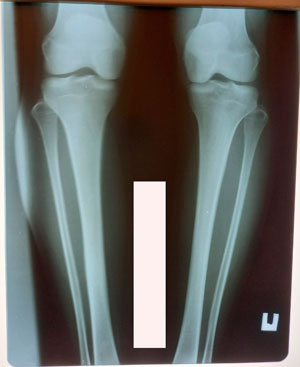

Исходник - 30 лет.

Дата операции - 25.12.2020

Диагноз: варусная деформация + Ротация с обеих сторон.